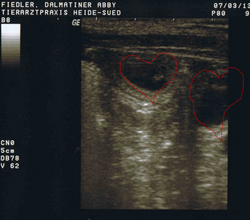

Heute, am 07.03. waren wir beim Ultraschall, und können berichten... Abby ist tragend, juchu!!!

Hier sieht man schon die kleinen Früchte, die bald zu zu kleinen Dalmatinern heranwachsen.